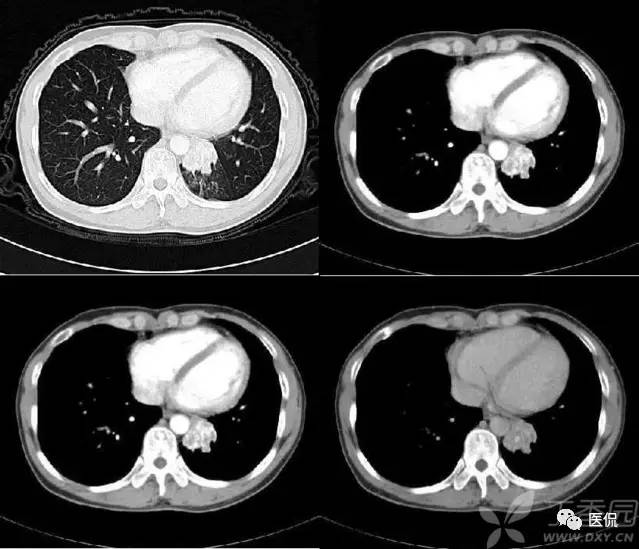

桃尖征

指肿块某一边缘尖角状突起形似桃尖,是炎性假瘤包膜的粘连牵拉,为良性肿块尤其是炎性假瘤特有。由于肿瘤大多位于肺的浅表部位,邻近胸膜常出现炎性反应,继之局限性的胸膜增厚、粘连,于肿物边缘可见类似胸膜幕状粘连的尖角状表现,这种尖角和肿块连在一起酷似一个桃子的桃尖。假瘤的主体和胸膜的炎性牵拉形成的尖角常常和周围胸膜、心包及纵隔粘连形成桥样结构及宽桥征;炎性假瘤的形成,一般被认为是感染后非特异性炎症的机化修复而引起的局限性慢性瘤样增生,形成的肿块压迫周围肺组织周围组织反应性改变,形成假包膜,所以一般边界广整,少数包膜不完整、无包膜或有胸膜粘连者,边缘可不光整。炎性假瘤依据细胞成分为组织细胞瘤型、硬化血管瘤型、浆细胞肉芽肿型、细胞上皮乳头痒增生等五个类型。肿块形态不规则和肿块分叶是病灶在病理上不同组织、不同数目因而生长速度不同所致;而边缘光滑的炎性假瘤则是同类组织以同等的生长速度增生形成。假瘤的分叶一般较浅或没有分叶,多为单发,两肺各叶均可发生,右侧多于左侧,下叶多于上叶。炎性假瘤可以有如下表现:

炎性假瘤桃尖征:

炎性假瘤(病灶形态不规则,边缘可呈刀切样,周围可见毛玻璃样改变,强化异常明显):

炎性假瘤(病灶边缘多发性空泡,表现为病灶边缘部位类圆形的光整的气体样低密度,是尚未被病变替代的肺结构支架,或病变坏死,这种空泡多位于病灶的边缘):